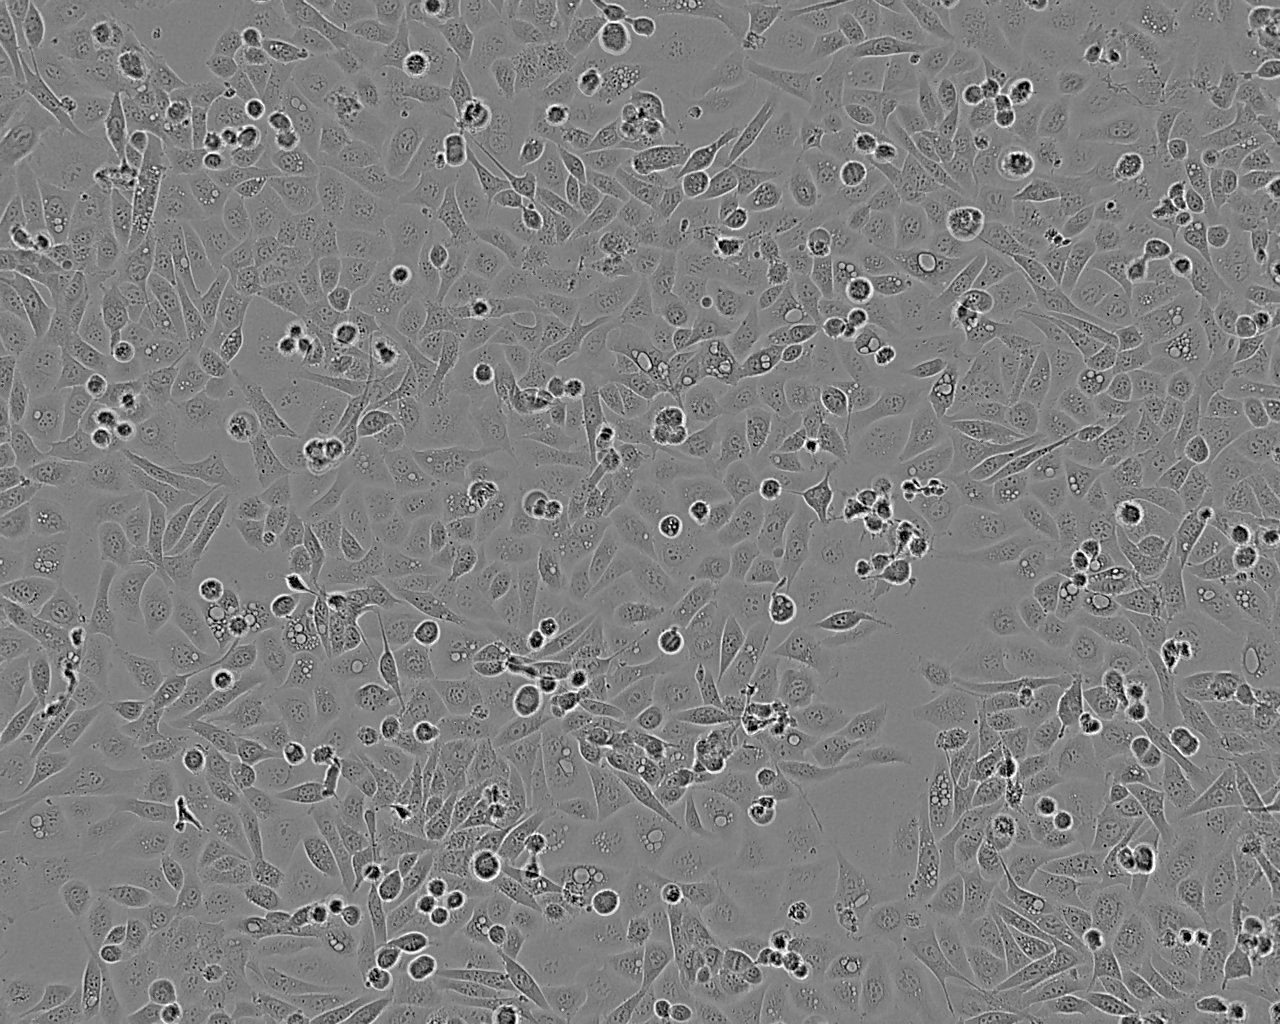

Cell Type

Epithelial

Split sub-confluent cultures (70-80%) 1:4 to 1:8 i.e. seeding at 1-3 x 10,000 cells/cm² using 0.05% trypsin or trypsin/EDTA; 5% CO₂; 37°C. Saturation density approx 10⁵ cells/cm².

Growth Mode

Adherent